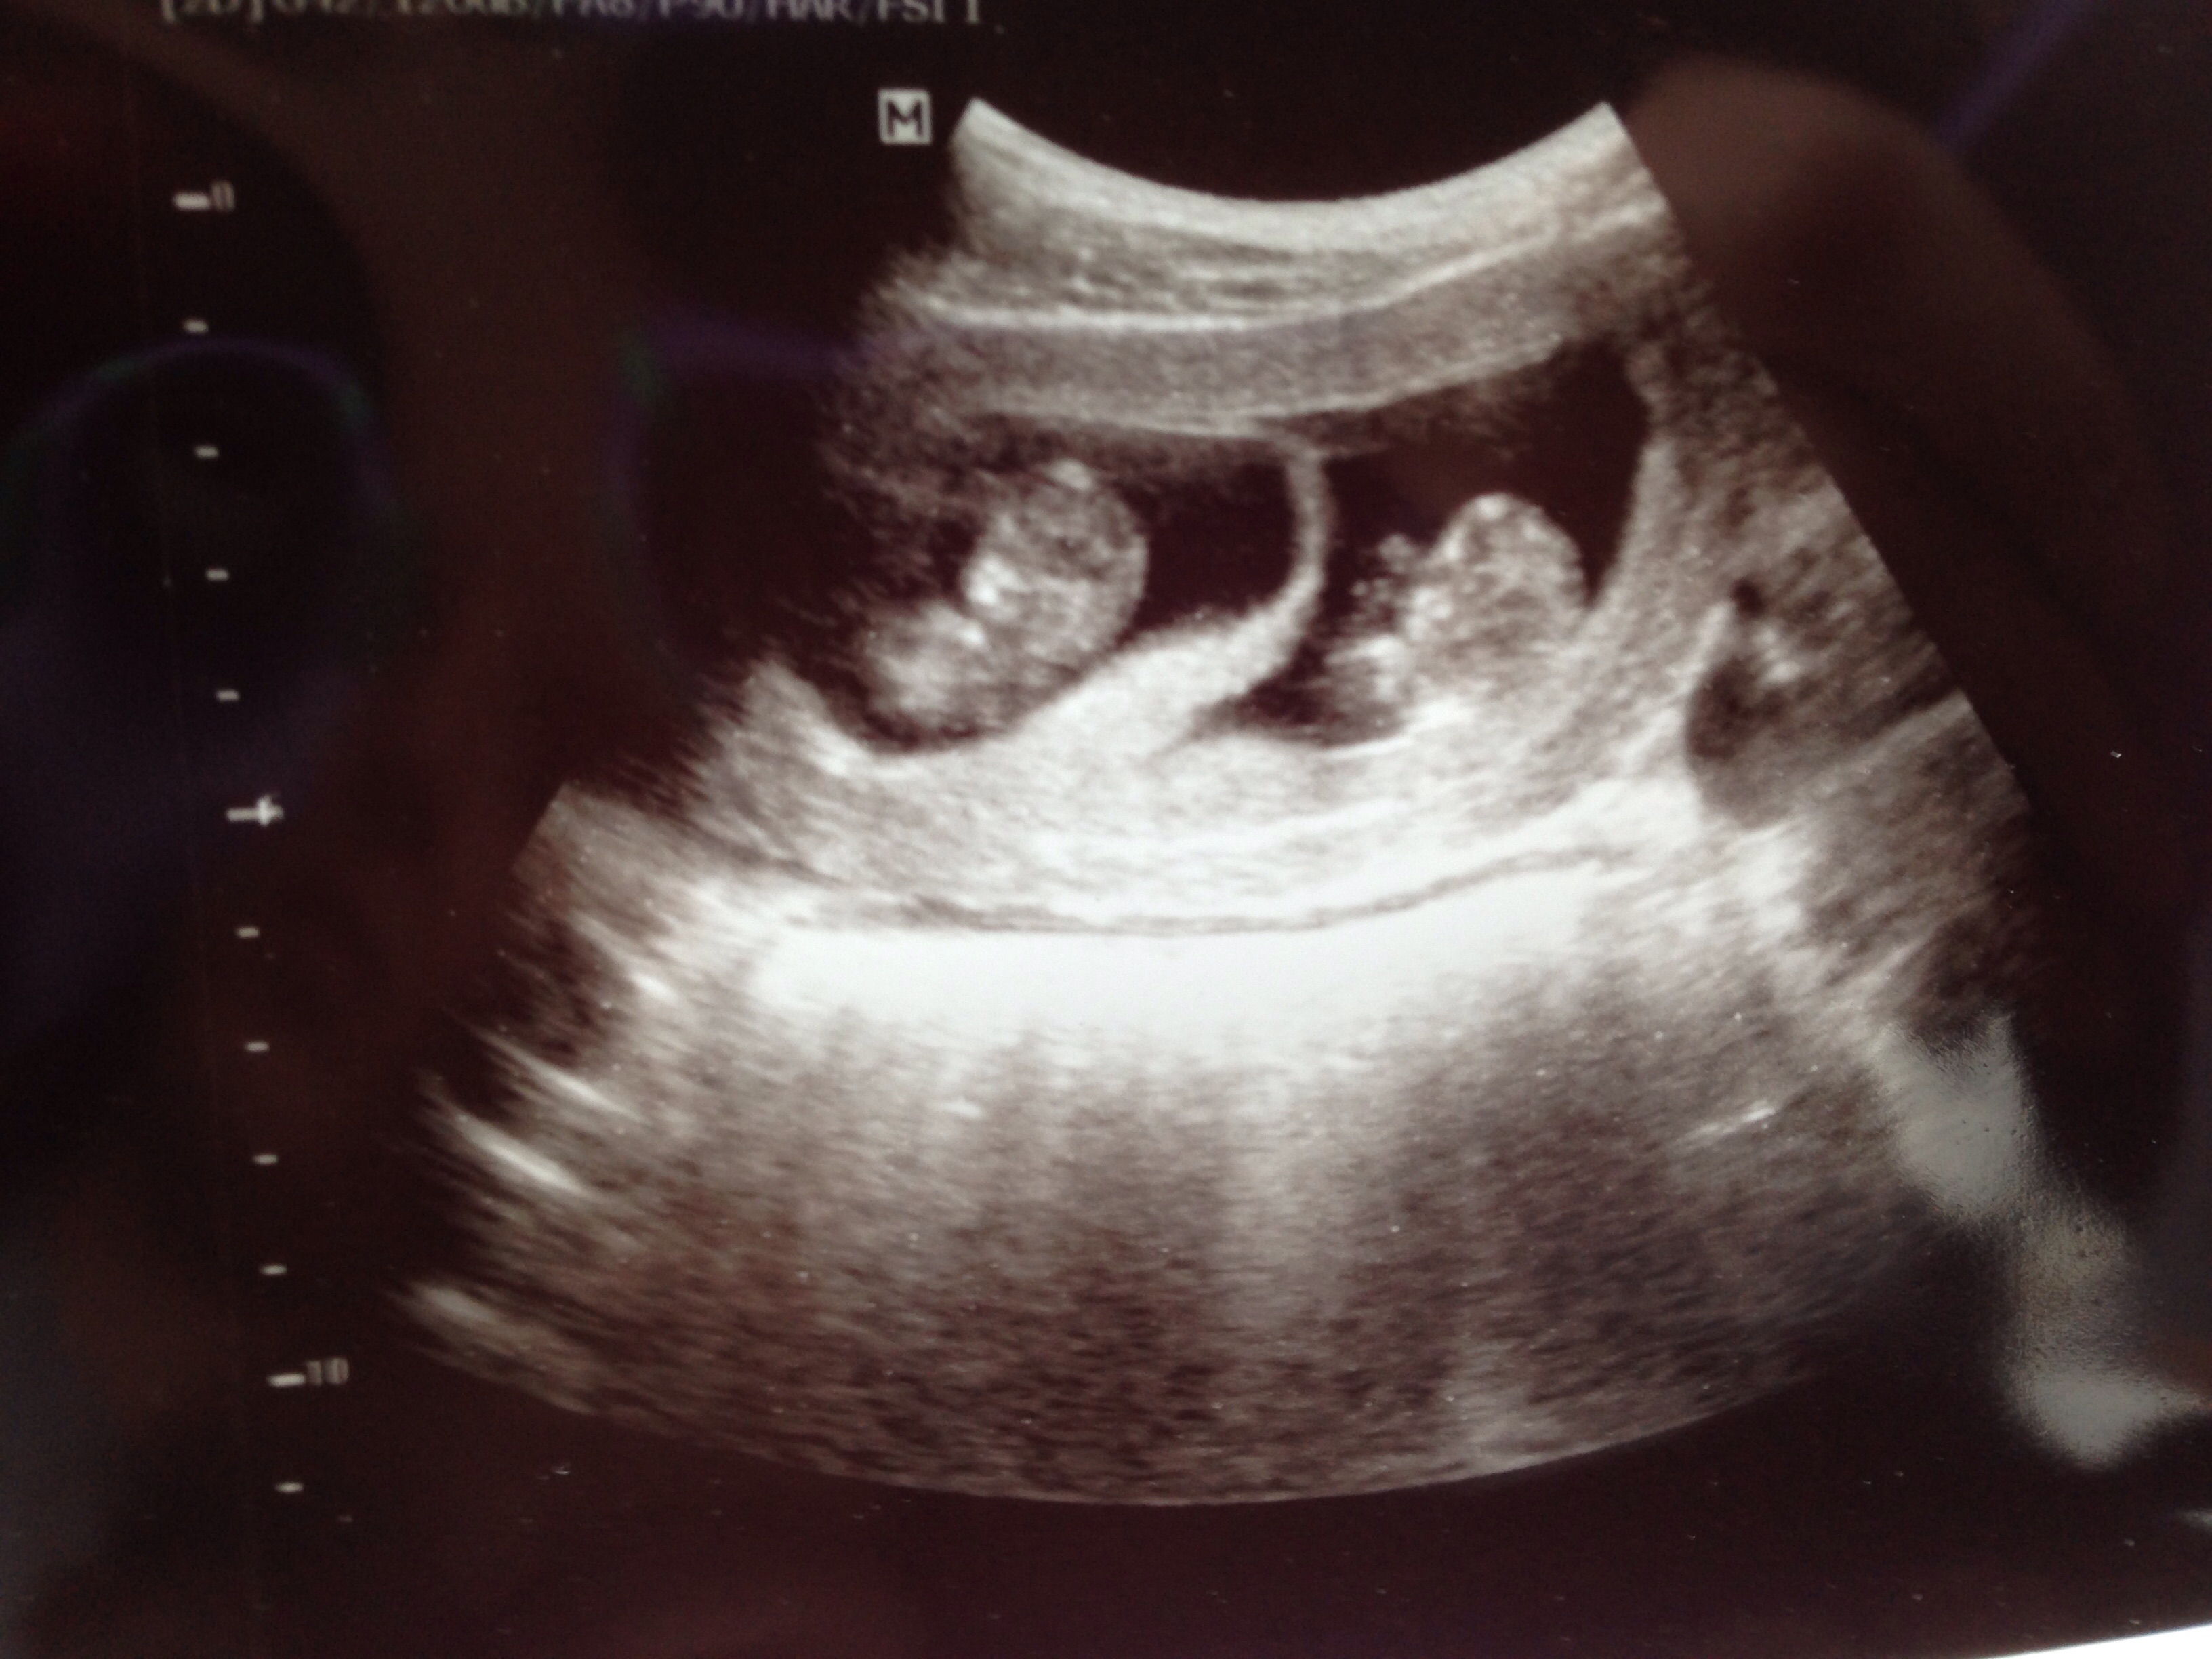

My baby at 11 weeks! Can't wait to have my 12 week scan on Tuesday

So cute! it is a perfect tiny baby!! How did you manage to get scans at 11 and 12 weeks? So jealous!! I can't wait to see our little passenger again next week. Thanks for sharing. Xo

This isn't a good picture (screenshot from video) but 12 weeks :x I love my little baby sooooo stinking much already! Look at its wittle nose! And I've said this at 10 w I'll say it again.... These legs are huge!!!